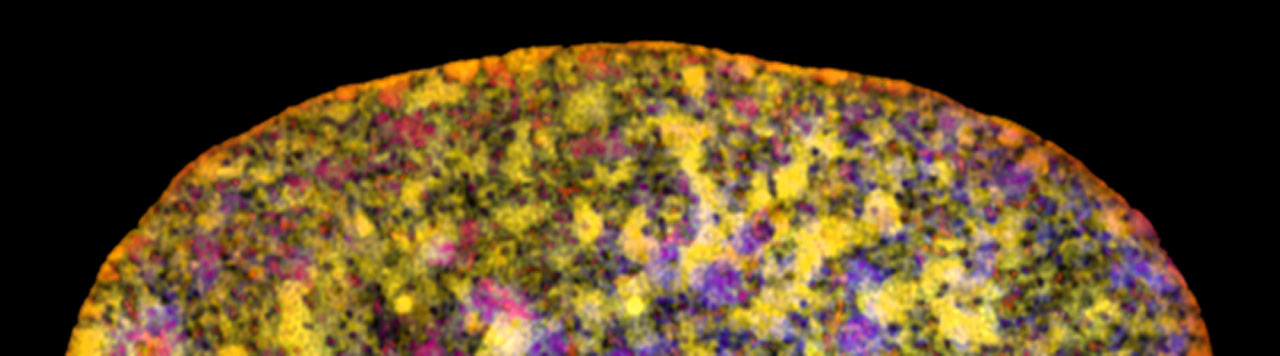

The search for the vulnerabilities of cancer cells

In order to find the vulnerabilities of cancer cells and treat cancer, we need to understand the biology of cancer. How do cancer cells differ from healthy cells, and how do they interact with their environment, or with therapies?

The Netherlands Cancer Institute has designated fundamental research as one of its five overarching research themes. Together, our researchers form a highly international, vibrant, and curiosity-driven community, working in close collaboration with the clinicians from our hospital towards one shared goal: tackling the huge societal challenge we call cancer.